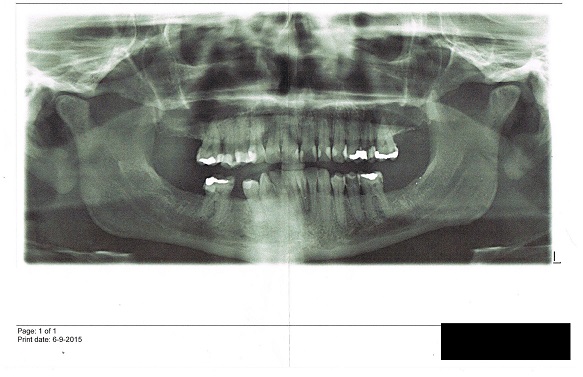

Deze tandarts kent mij niet dus ik dacht misschien handig een overzicht foto mee te nemen (2maanden terug gekregen tijdens bezoek aan spoeddienst).

Deze foto laat ik zien aan deze tandarts (pardontoloog)

tot mijn grote schrik blijkt mijn gebit in een parodontitis kaak te staan er is zo veel kaakbot verloren gegaan dat behoud van mijn gebit niet mogelijk is volgens deze tandarts .nu is door de val tand los komen te staan maar dit had sowieso niet lang meer geduurd.

Op zich is elk probleem ook aan een leek goed uit te leggen. Gaatjes en slecht aansluitende vullingen kan je op een foto laten zien, met uitleg waar je op moet letten en naar moet kijken. Daarnaast is een foto alleen nooit heilig.

Hetzelfde geldt voor parodontale problemen.

Ook is altijd het verloop in de tijd van belang, dus liefst oude foto's en zo erbij.

kort samengevat : beide tandartsen zelfde foto van 6 september 2015

tandarts 1 : geen ernstige parodontitis /botafbraak ( 16 oktober 2015)

tandarts 2 : ernstige parodontitis / drastisch botafbraak prothese noodzakelijk (24 november 2015

even globaal, en alleen van foto zonder mondonderzoek: GEEN indicatie voor totaalextractie en kunstgebit..Wel enig botverlies, maar lijkt mij nog niet in de categorie ernstige parodontitis. Leeftijd is ook een factor (beeld foto is minder ernstig voor/ bij iemand van 60 dan bij iemand van 30..). Er is sprake van parodontitis, maar kan ook best zijn dat ie niet meer actief is en de schade al jaren geleden gebeurd is en nu al weer even stabiel. Daar is dossier voor nodig en oude foto's. Gezien de botlijn twijfel ik eraan of het echt een nog actief proces is.

Het is jammer dat ik de foto niet kan vergroten/bewerken.

Probleem ondersnijtand is relatief eenvoudig oplosbaar denk ik.

wel een gebit waar wat werk aan is, als je heel lange termijn gaat kijken. Oorzaak/reden van verlies van de diverse kiezen is daar wel een factor in, factor roken ook, algemene gezondheid etc etc. Oftewel lange termijn plan maken waar alle factoren in meegenomen zijn. Maar op het oog lijkt mij alleen verlies van 1 ondersnijtand onvermijdelijk. Naast de OP zijn ook diverse solofoto`s onontbeerlijk.